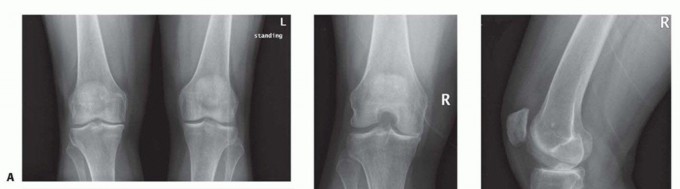

DEFINITION Unicondylar knee arthroplasty (UKA) is a surgical treatment alternative to total knee arthroplasty…